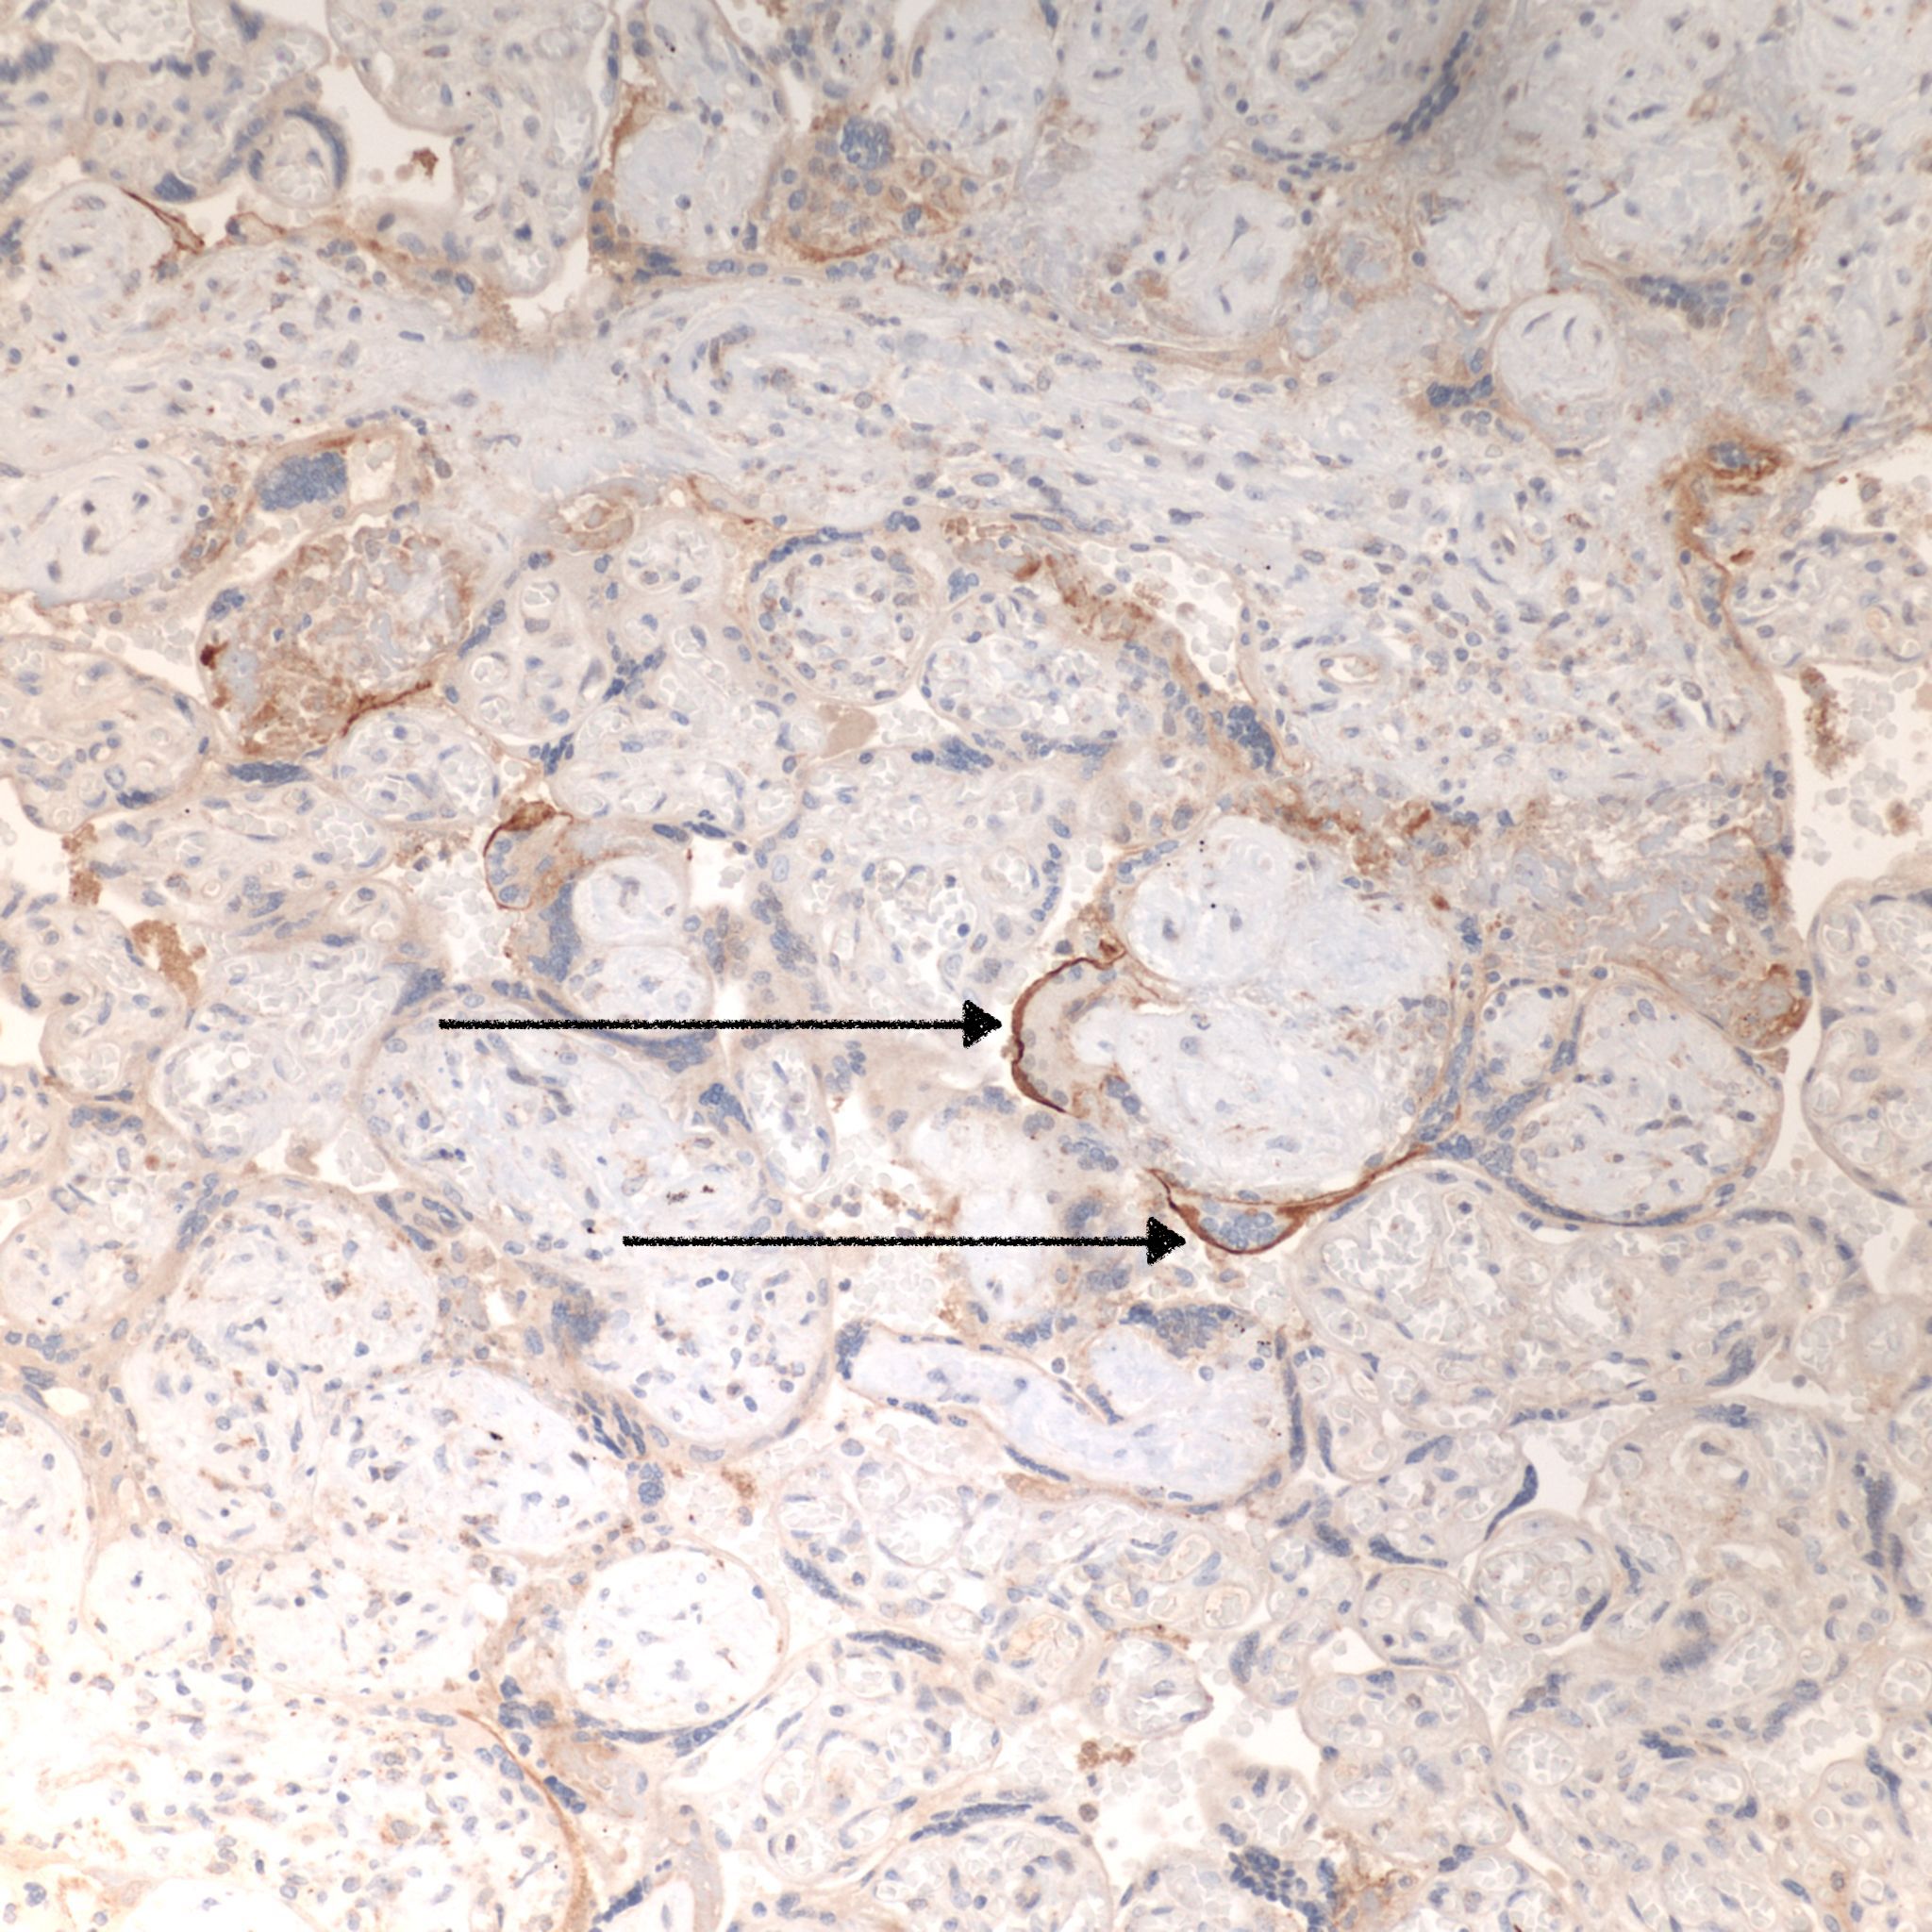

CHIV associated with Villitis of Uknown Etiology (VUE)

This pattern could be due to a primary cause of VUE with incidental chemotaxis of monocytes, two pathogenetically interrelated processes, or an incidental focus of VUE in a predominant CIIV disease. Currently, describing the extent of each process and its colocalization or lack of may prove useful until a better way to classify the co-existing lesions can be developed. One study has shown that there is a dichotomy between cases with c4d staining and those without c4d staining18.

Villitis of Unknown (A)Etiology (VUE): See entry on villitis of unknown aetiology, and pathogenesis below. As with perivillous fibrinoid, the relationship of VUE to the intervillositis is still not understood. Villitis of unknown aetiology villitis, if independent of intervillositis, would be present in the same percentage of cases as in the general population, around 6%. There is both observational evidence and potential pathogenetic relationships between villitis and intervillositis. An association of the two lesions is probable.

C4d: to show evidence of complement fixation on the microvillous surface of the syncytiotrophoblast. While further study is needed, the subclassification of intervillous monocyte accumulations into those with and without complement fixation and the subclassification of villitis of unknown aetiology with intervillous monocytes into those with and without complement fixation may prove to be a useful distinction.

6. Villitis of unknown etiology (VUE) and intervillosits. Our current understanding of VUE is that the pattern of inflammation is due to a vasocentric attack by maternal T cells on villous capillaries. Since the interior of the villus does express HLA alloantigens, such a rejection response is plausible. How these lymphocytes breech the syncytiotrophoblastic barrier is not clear. Theoretically, gaps due to injury in the syncytiotrophoblast could allow entry. A perivillous fibrinoid response which is not only fibrin, but the normal substances secreted by cytotrophoblast at maternal interfaces, such as fetal fibronectin and annexins, may normally be a sufficient barrier to prevent maternal T lymphocyte entry into the villous. However if syncytial necrosis in intervillositis was rapid and extensive, a breach for T lymphocytes maybe created that could account for the association of the two lesions. In this case, the villitis would be secondary to the intervillositis. The finding of c4d staining in some cases of the mixed lesion supports this hypothesis. In other cases, the two lesions may be independent. VUE is common placental finding likely for multiple different etiologies. There may be value to noting if the intervillositis and villitis are in the same or contiguous areas, and positive c4d staining may also demonstrate a causal connection. VUE with intervillositis may like fibrinoid be a measure of severity and extent of the syncytial injury.